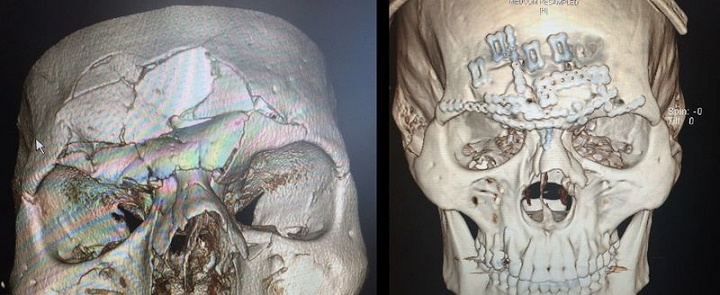

Hôm 16/7, trong trận đấu thuộc sự kiện Bellator 158, Cyborg bị lõm hộp sọ vì bị võ sĩ Michael Venom Page thúc đầu gối cực mạnh lên trán.

Đến ngày 27/7, anh được phẫu thuật ở Los Angeles (Mỹ), gắn cố định các miếng nẹp chuyên dụng lên hộp sọ. Trên đầu Cyborg có vết mổ kéo dài từ mang tai bên này sang mang tai bên kia.

| Hình 3D hộp sọ của Cyborg trước và sau phẫu thuật. |